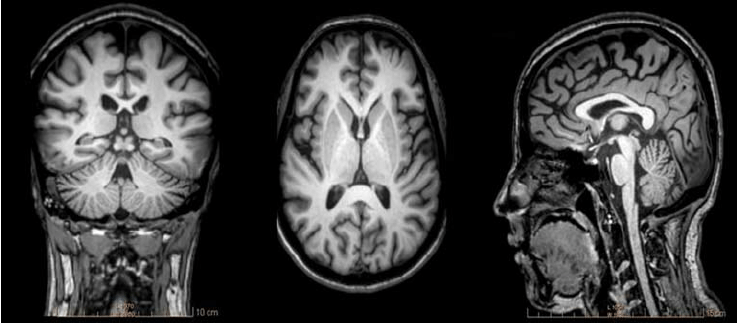

Q

what type of imaging is this?

CT

MRI T2

PET

Ultrasound

MRI T1

A

what type of imaging is this? CT MRI T2 PET Ultrasound MRI T1

what type of imaging is this? CT MRI T2 PET Ultrasound **MRI T1**

35